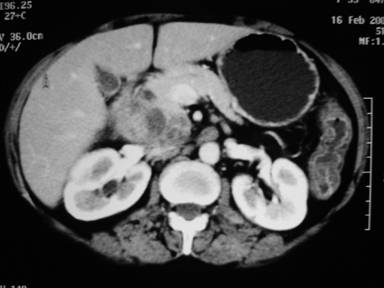

A 59-year-old woman presented with complaints of continuous, non-radiating type upper abdominal pain for the past 6 months. Other symptoms were early satiety, anorexia and 5.5 kg weight loss over last 4 months. The patient did not have fever, jaundice or gastrointestinal bleeding. She gave a history of pulmonary tuberculosis 10 years back for which she took antituberculous drugs for 9 months. Physical examination revealed pallor. Rests of the physical examinations were unremarkable. Investigations showed hemoglobin of 8.9 g/dL (reference range: 13.2-16.2 g/dL), total leukocyte count of 6,700 mL-1 (reference range: 4,000-11,000 mL-1) with a normal differential count, erythrocyte sedimentation rate of 60 mm/first hour (reference range: 0-17 mm/first hour). Liver function tests were normal. Results of HIV serology were negative, and results of chest radiograph were normal. A CECT abdomen (Figure 1) showed a mass in the head of the pancreas with multiple conglomerate peripancreatic lymph nodes and was associated with central necrosis. Portal vein was encased by the mass. Based on CT scan, the mass was non resectable and we advised CT guided FNA from the mass for consideration of chemoradiotherapy. FNA (using 22 G needle) from the peripancreatic lymph nodes showed epithelioid cell granuloma and caseation necrosis. Ziehl-Neelsen stain revealed acid fast bacillus (Figure 2). The patient received antituberculous therapy for 6 months. The patient was well at the 48-month follow-up.

Figure 1. CECT abdomen showing a mass in the head of the pancreas with necrosis (Case #1). |